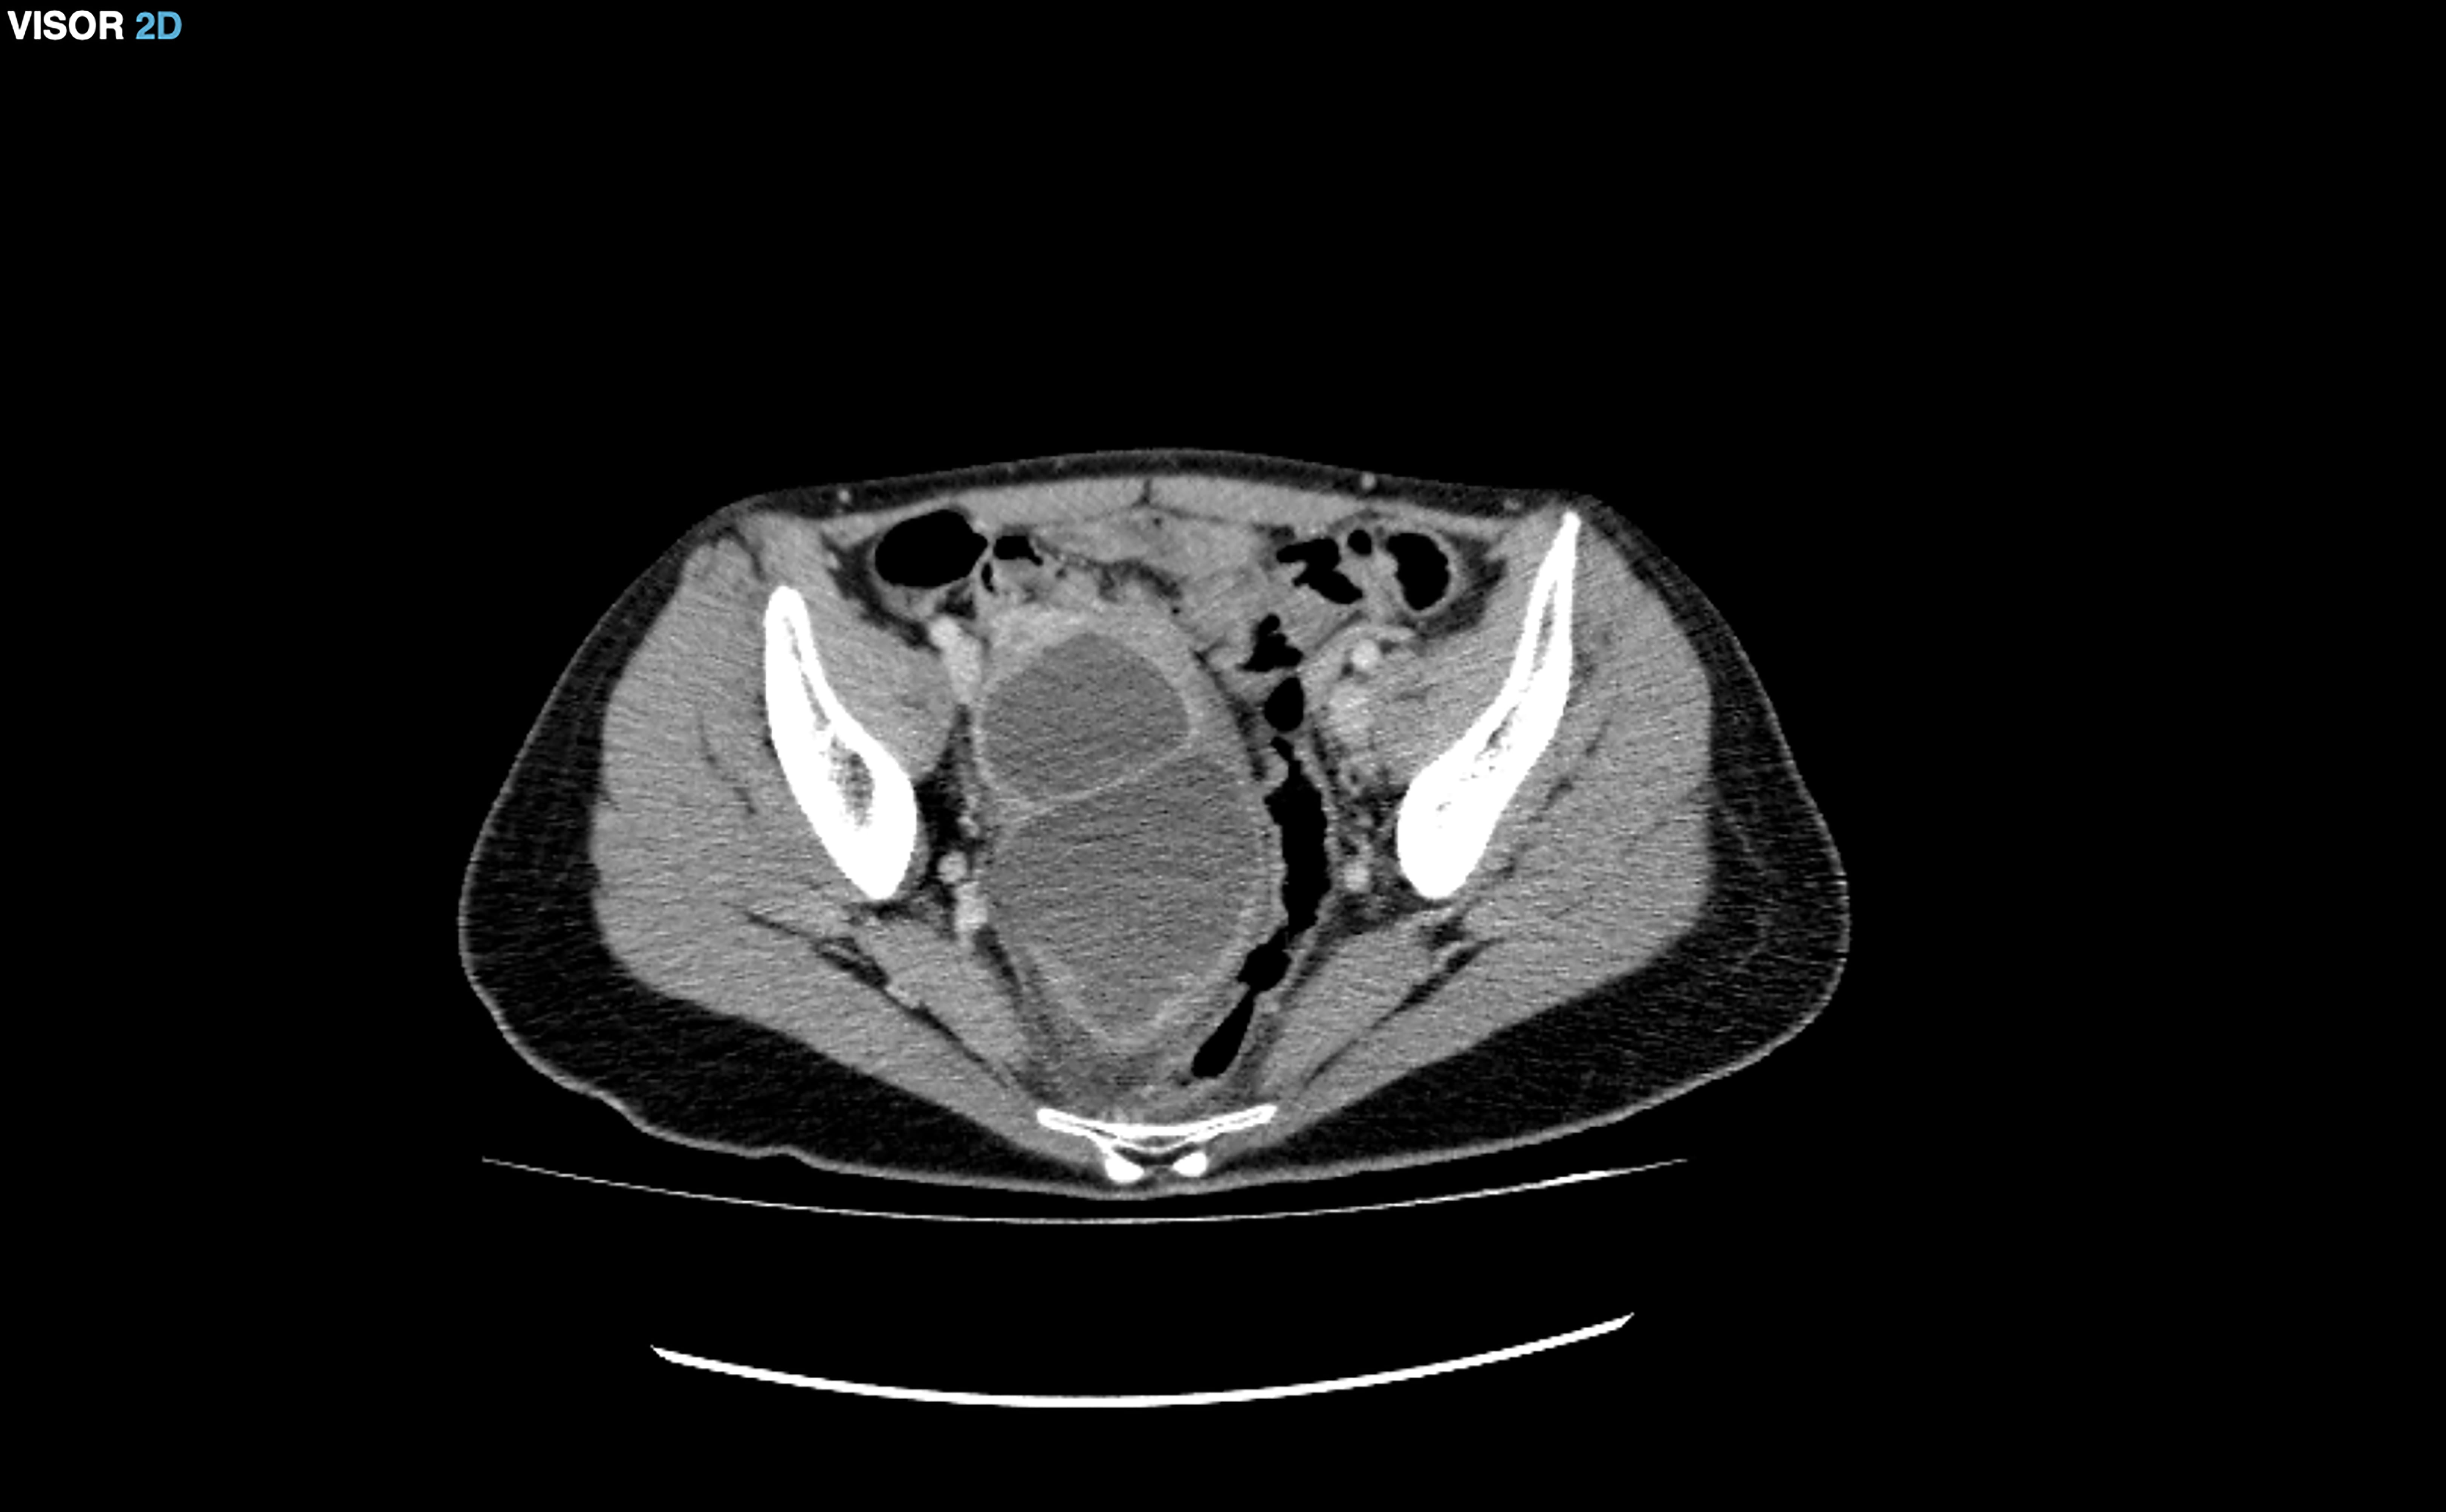

However, 11 days later, she came back to the emergency department due to

recurrent abdominal pain and high fever. Her white blood cell count was

20,000/mm

Fig. 1.Right tubo-ovarian abscess.

Endocervical and vaginal cultures were positive for Enterococcus faecalis. The patient received intravenous antibiotic treatment with ceftriaxone, doxycycline and metronidazole without clinical improvement, so a percutaneous drainage of the abscess was performed by interventional radiology, obtaining a positive culture for E. coli infection. The antibiotic treatment was changed to piperacillin-tazobactam. The patient remained afebrile after abscess drainage. Several ultrasounds were performed during her admission to check the drainage and evolution of the abscess. She was discharged 8 days after drainage with a complete resolution of the abscess. Finally, she had a negative beta-hCG test after the resolution of the PID.